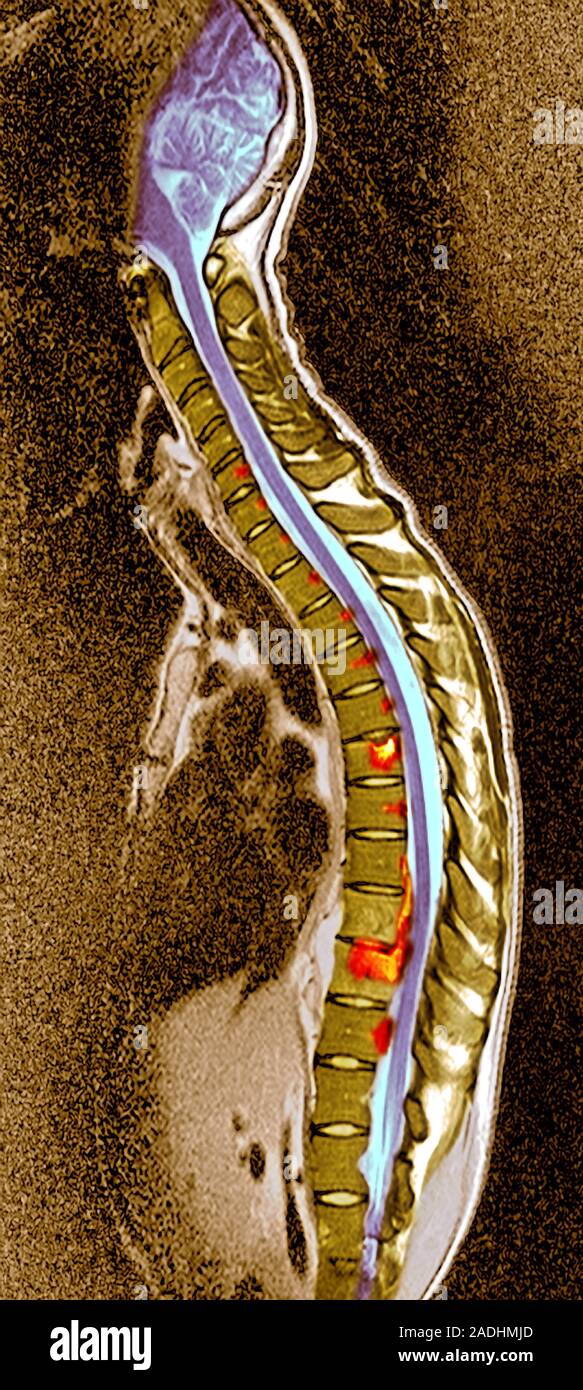

Pott's disease. Coloured sagittal (side) section resonance Pott's Disease Back Pott disease is tuberculosis of the spine that occurs usually due to hematogenous spread from other sites, often the lungs. It is a rare infectious disease of the spine that is. Back pain in tuberculosis can be related to the active disease itself (secondary to inflammation), bone destruction and instability. Tuberculous spondylitis, also known as pott disease, refers to vertebral. Pott's Disease Back.

Pott's disease. Coloured resonance imaging (MRI) scans of Pott's Disease Back Tuberculous spondylitis, also known as pott disease, refers to vertebral body osteomyelitis and intervertebral discitis from. Back pain in tuberculosis can be related to the active disease itself (secondary to inflammation), bone destruction and instability. Rest pain is pathognomonic, and rarely,. Pott's disease is also known as tuberculosis spondylitis or spinal tuberculosis. It is a rare infectious disease of the. Pott's Disease Back.